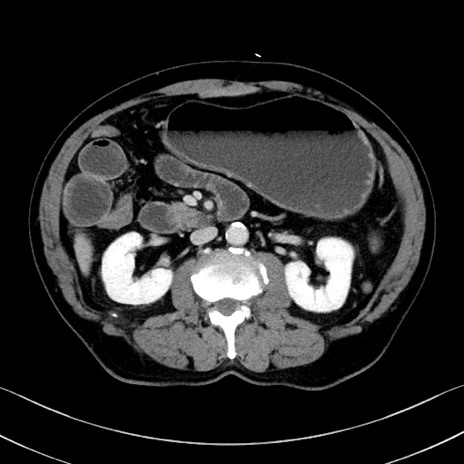

症例

冠状断像

【症例】70歳代 男性

【主訴】腹部膨満、嘔吐

【現病歴】昨日より腹部膨満感出現。本日増悪し、仙痛出現。嘔吐あり、受診。

【既往歴】糖尿病、胆摘後

【身体所見】BP 149/80mmHg、HR 74/min、BT 35.9℃、腹部:膨満、軟、圧痛なし。腸雑音減弱あり。上腹部正中切開瘢痕あり。

【データ】WBC 13500、CRP 1.72